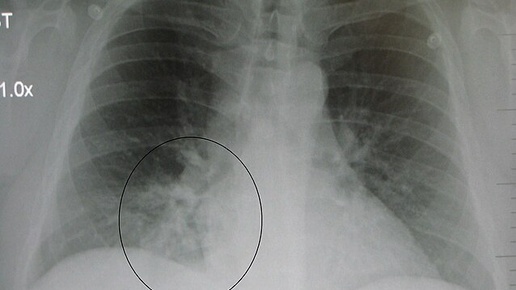

✨Пневмония – это воспаление легочной ткани, которое вызвано вирусами, бактериями, грибами и др. Что еще может быть? ‼️Однако тут важно понимать, что вести ребенка «послушаться» особенно в первые дни заболевания не имеет смысла, так как врач может и не «услышать» пневмонию при осмотре. Речь не идет о том, что врач плохо проводит аускультацию, а о том, что даже опытный врач не всегда слышит эти признаки потому что вирусные пневмонии вообще не слышны в большинстве случаев, так как при них обычно нет уплотнения легочной ткани, которое и дает изменение звука при аускультации...

Пневмония у детей гораздо более выражена, чем у взрослых. Из-за ещё не сформировавшейся иммунной системы ребенка, развивается она очень быстро. ● ● ● Симптомы пневмонии у ребенка во многом зависят от того, что вызвало болезнь. Пневмонию чаще всего вызывают бактерии или вирусы, но виновником также может быть грибок. Какие симптомы могут указывать...